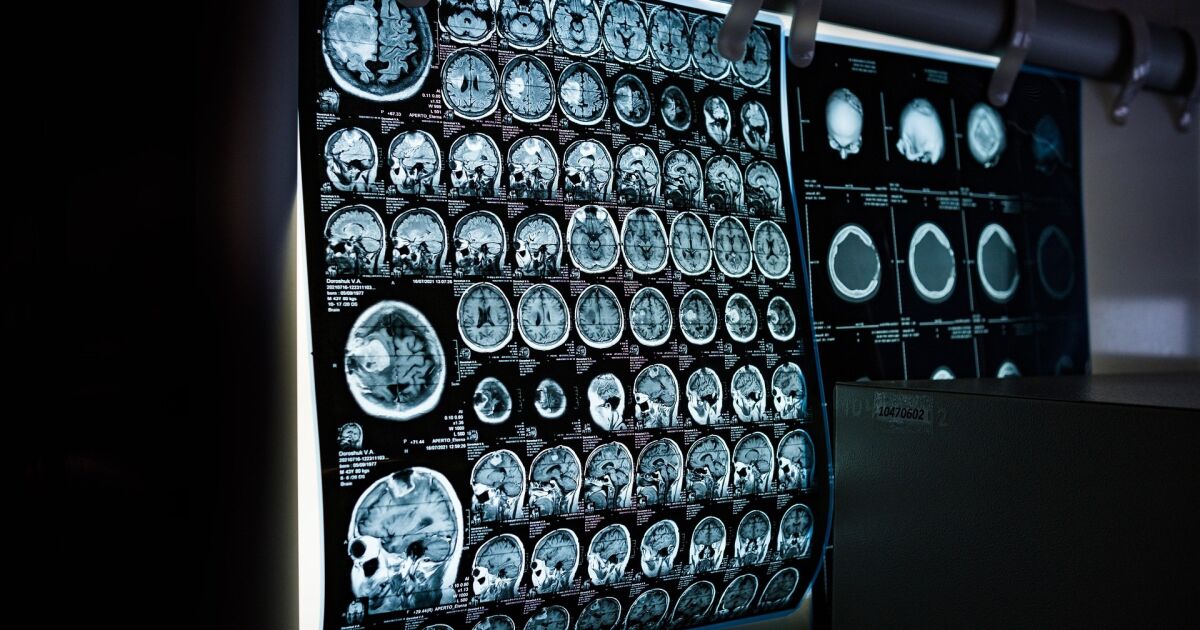

Множествената склероза все още е заболяване с неизвестен причинител и за съжаление продължава да няма лечение. Терминът означава „много белези“ и се отнася до областите, които се появяват върху мозъка и гръбначния мозък, след като миелинът, покриващ нервите ни, е увреден.